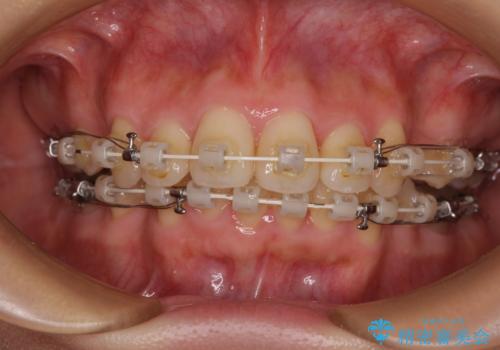

- 矯正装置

- 審美装置

- 奥歯も含めて全体的なデコボコと前歯の突出感を気にして来院された患者様です。

上下左右第一小臼歯4本を抜歯し、ワイヤー装置にて矯正治療を行うこととしました。

想像以上に咬合力が強く、抜歯したスペースを閉じきるまでに長期間を要することとなりました。

前歯の突出感がなくなり、仕上がりには大変満足していただけました。